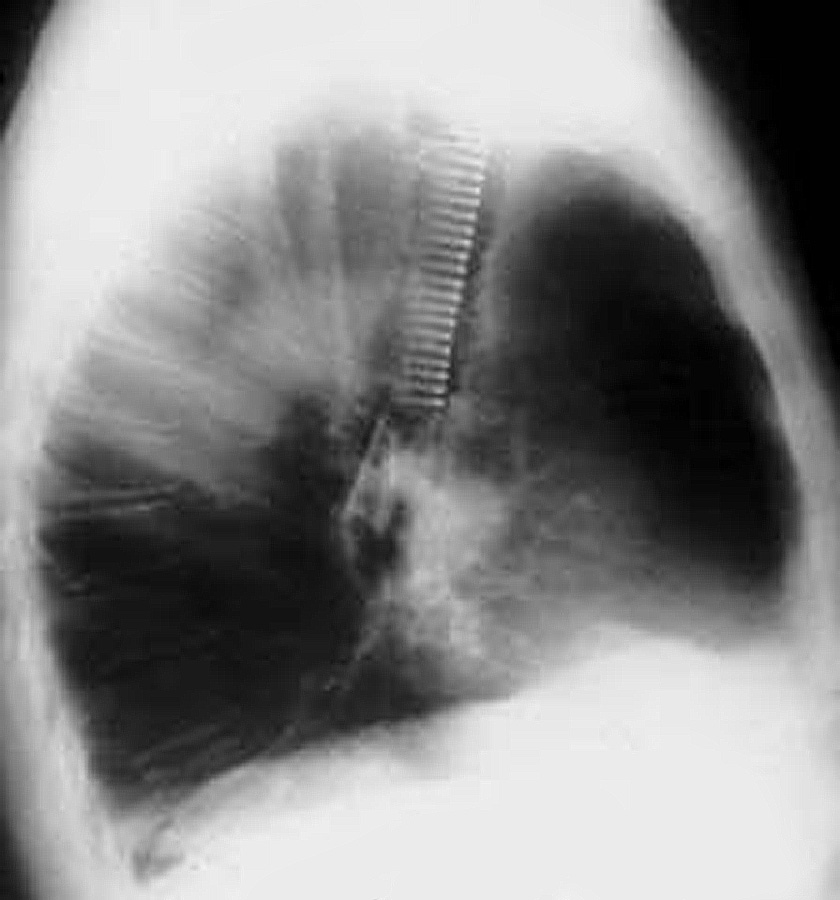

Freitag and colleagues extensively described the use of the Dynamic stent (Figures 15, 16) in patients with benign and malignant airway obstructions. This stent shows the potential advantage of having a flexible “membranous wall” able to squeeze down during coughing, facilitating mucous clearance. Placement of this stent is potentially more complicated but dedicated delivery grasping forceps have been designed to facilitate it (Figure 17). Results are promising for management of distal tracheal, carinal, and mainstem bronchial obstructions.

![]() |

| Figure 15: Dynamic Freitag stent | Figure 16: Chest x ray: lateral view with the Dynamic stent in place | Figure 17: Dedicated Dynamic stent introducer |